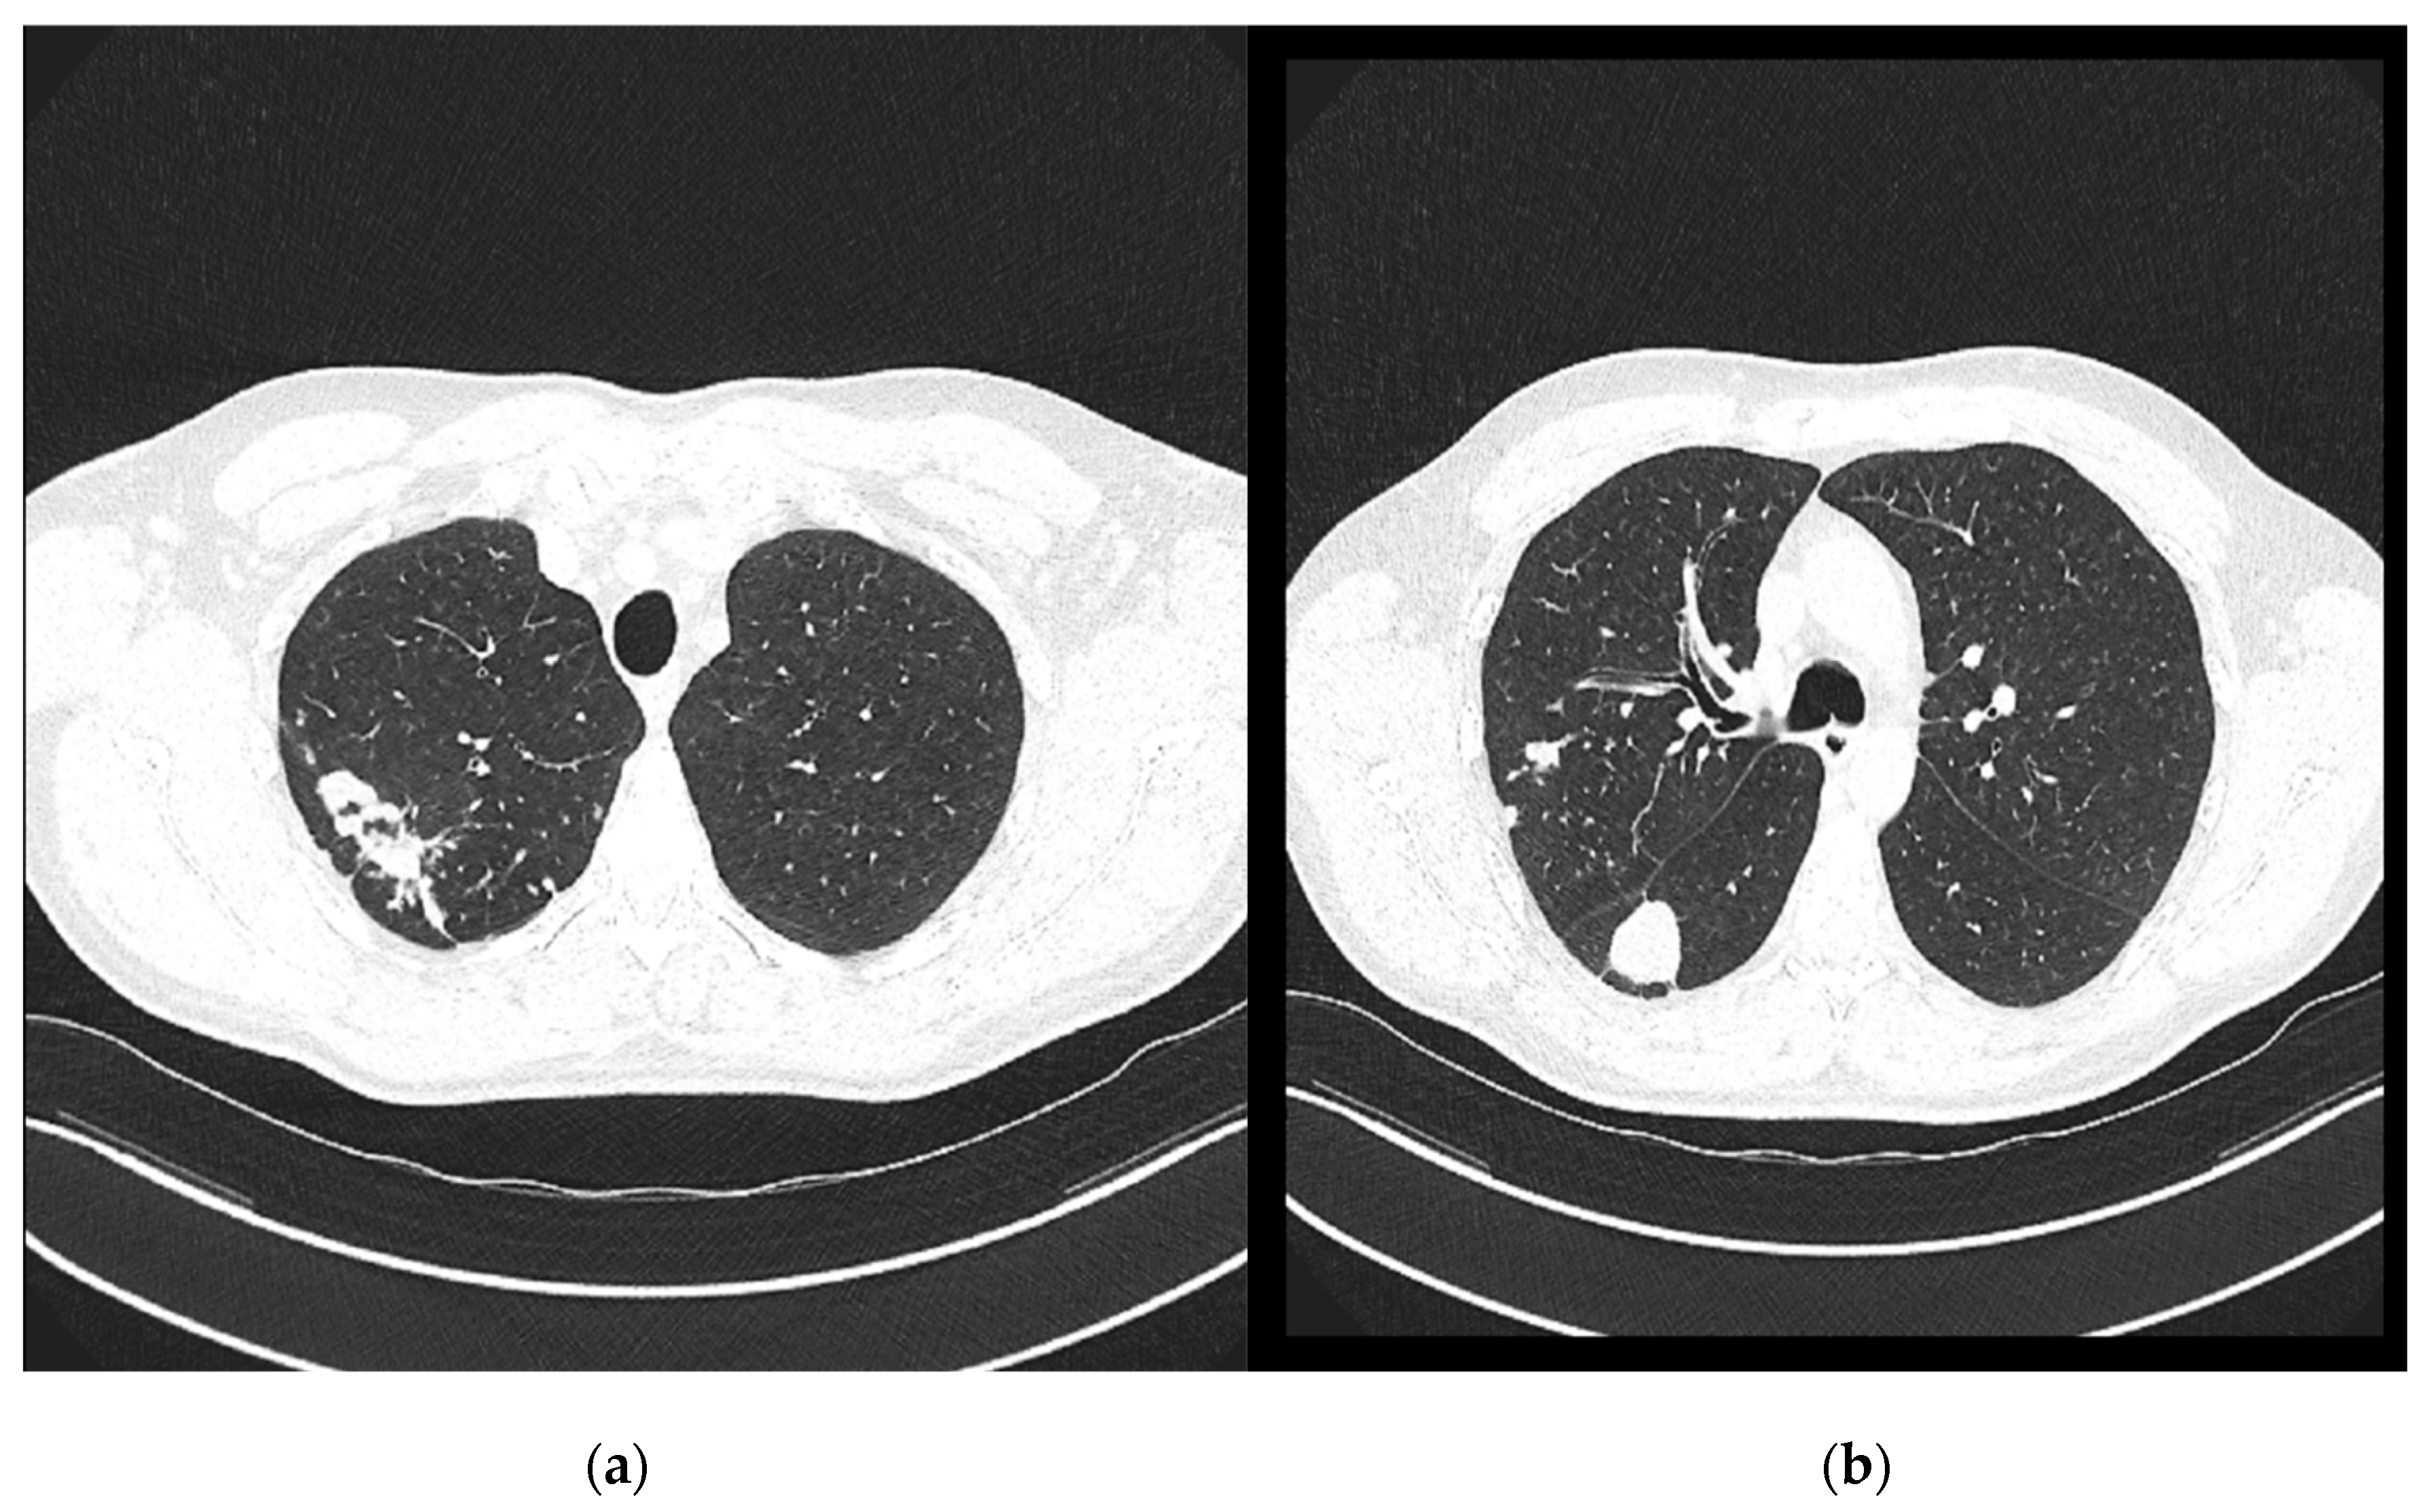

Chest computed tomography (CT) revealed numerous small confluent nodular lesions in the apical and posterior segments of the right upper lobe, forming a characteristic “tree-in-bud” pattern. These lesions ranged in size from a few millimeters to 2–3 cm and surrounded a cavitary lesion measuring up to 43 mm, adjacent to the pleura. A 3 cm nodular lesion with small calcifications was also observed in the upper segment of the right lower lobe, accompanied by a similar but less pronounced “tree-in-bud” pattern (Figure 2).

Figure 2. Chest CT scans (29 April 2024): (a) large cavitary lesion in the right upper lobe; (b) nodular lesion in the lower lung lobe and a discrete “tree-in-bud” pattern.